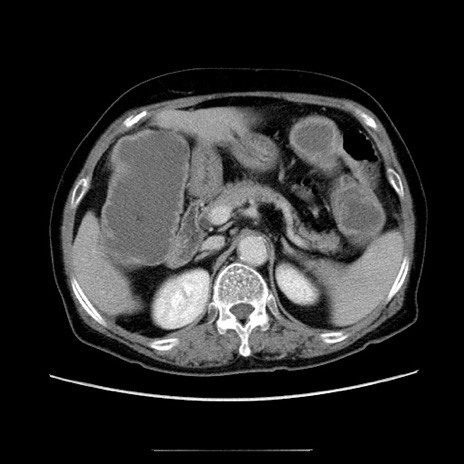

症例5(横断像)

【症例】70歳代女性

【主訴】お腹が張る

【現病歴】1週間くらい前から腹部膨満の自覚あり。昨日夜から増悪したため、本日救急外来受診。

【身体所見】意識清明、BT 36.5℃、BP 165/106mmHg、HR 80bpm、SpO2 98%、腹部:膨満、軟、自発痛・圧痛なし、触診にて不快感あり、腸蠕動音:減弱

【データ】WBC 12600、CRP 1.04